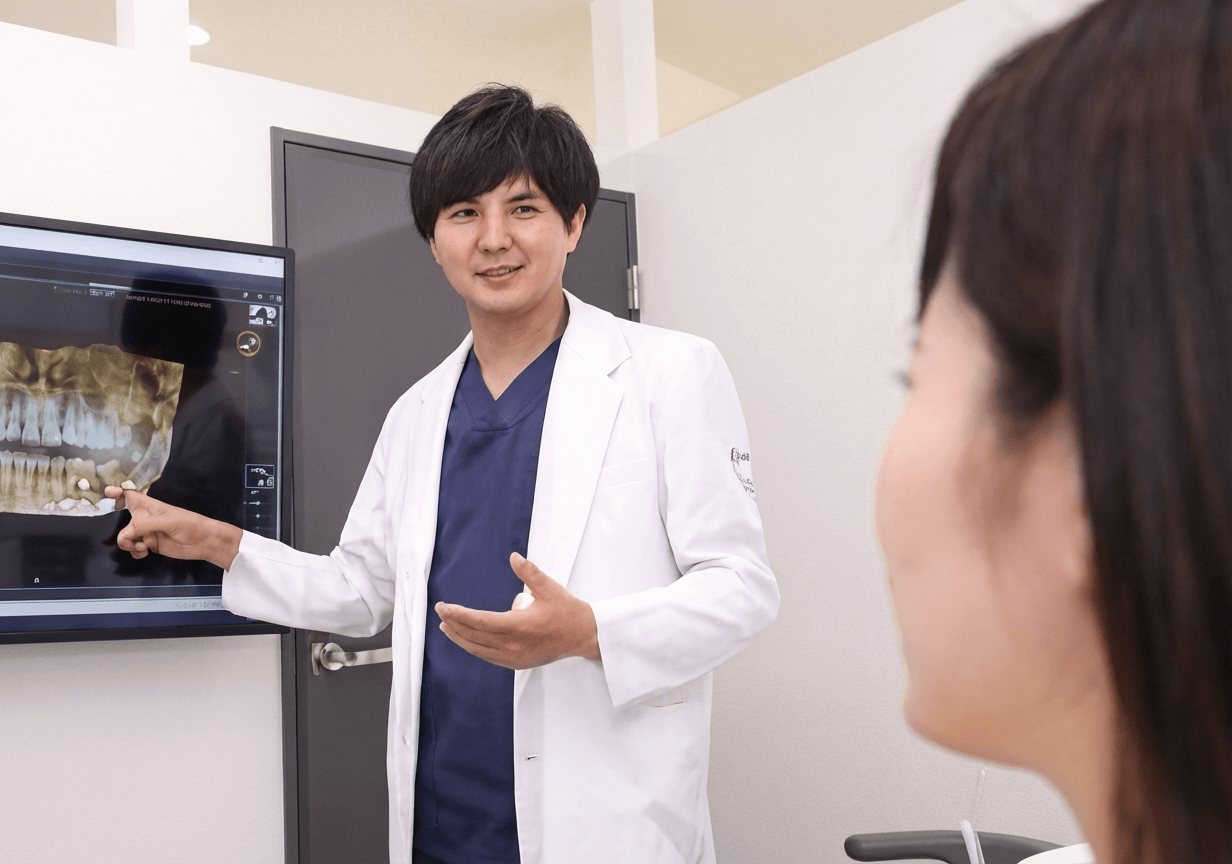

カウンセリング・診察

患者様のお口の悩みや治療のご希望をお伺いし、レントゲン等を撮影。現在のお口の状態を確認します。

治療計画の立案

検査結果を基に、患者様一人ひとりに最適な治療計画をご提案します。